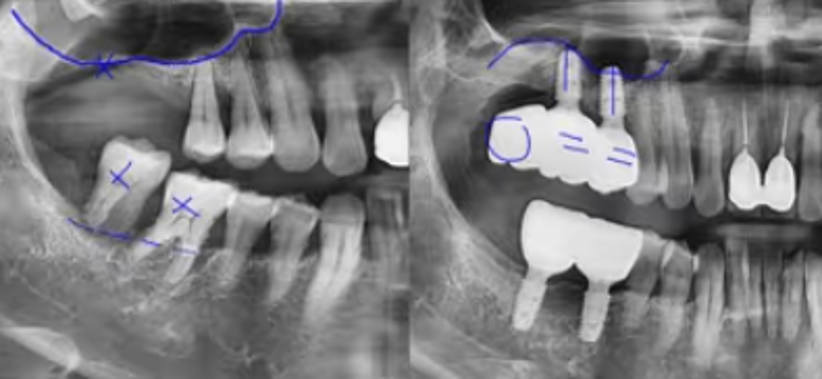

CASE.5 잇몸뼈가 없다면, 상악동거상술